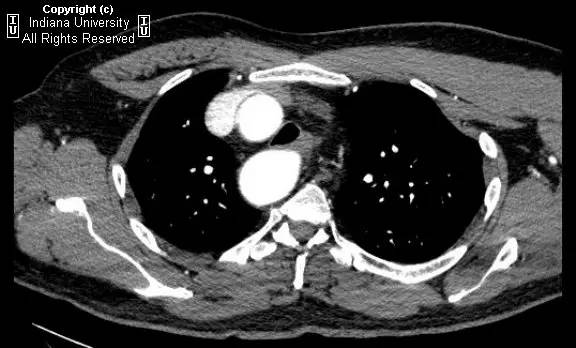

【影像学表现】胸部平片示右位主动脉弓,肺动脉突出,双肺清晰。CT示右位主动脉弓,并右位降主动脉,迷走左锁骨下动脉起自后方,从食管后走形形成血管环。迷走左锁骨下动脉与憩室相关(Kommerell)。食管因左锁骨下动脉及憩室而向前移位。

【诊断】右位主动脉弓并血管环形成、迷走左锁骨下动脉并Kommerell憩室

Right-sided aorticarch, with vascular ring and aberrant left subclavian with Kommerell\’sdiverticulum